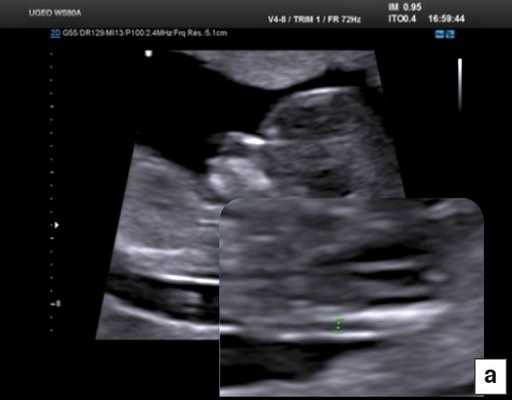

В начале 90-х годов прошлого века в практику был внедрен метод измерения толщины воротникового пространства (ТВП) в I триместре беременности, и к настоящему времени его считают показателем не только анеуплоидии, но и широкого спектра наследственных синдромов и пороков развития [2]. K. Николаидес (K. Nicolaides) с группой исследователей предложили новую модель скрининга на анеуплоидию и установили правила использования этого метода, в частности необходимость применения кривой обучения, проведения аудита, качественного (процедура оценки качества изображений) и количественного (медиана, дельты-ТВП и т.д.). Фонд медицины плода (Fetal Medicine Foundation) стандартизировал предложенный ими клинический протокол и установил правила сертификации для повышения качества медицинской помощи и уменьшения изменчивости результатов данных скрининга [3, 4]. Измерение ТВП можно проводить вручную (рис. 2a) или полуавтоматически (рис. 2b), чтобы результаты измерений были более воспроизводимыми. Кроме того, компания Samsung разработала дополнительный метод измерения показателей ТВП - 5D NT, позволяющий точно выявить срединно-сагиттальную плоскость и улучшить оценки по шкале Германа (Herman score).